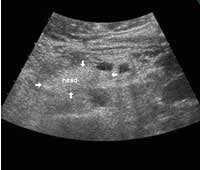

While an anatomic atlas is helpful for obtaining a detailed description of the morphology of the pancreas, I will also discuss the anatomic landmarks that are important from the sonographer's point of view. The pancreas is located in the epigastrium and has an oblong shape, oriented transversally across the midline. The main parts of the pancreas are the head with the uncinate process and the dorsal bud to the right, the body in the middle and the tail to the far left. The longest part of the pancreas is located to the left of the midline, with the tail near the splenic hilum usually slightly above the head. There are no clear demarcations between the different areas, though sometimes the dorsal bud of the head is darker, with sharp delineation compared to the rest of the pancreas.

- The lower end of the uncinate process is often overlooked, probably because of its tapered form, which makes it blend with the surrounding fat tissue and the duodenum. Longitudinally, the head of the pancreas is often around 7 cm long, and pathology of the pancreas is often located in the difficult bottom area.

The following study describes anatomical landmarks in the ordinary pancreas of a thin patient:

Transverse planes in caudal direction: